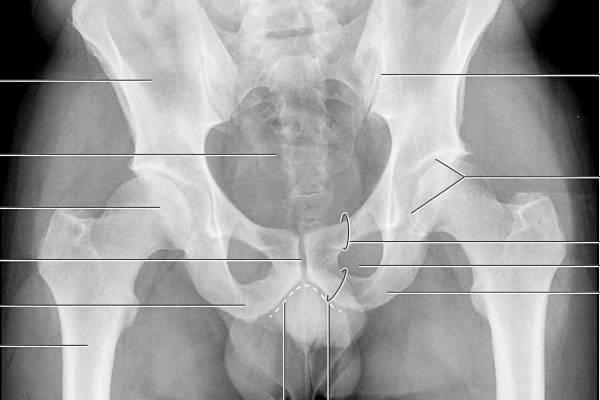

Диагностика мышечно-скелетной боли призвана исключить факторы риска, которые без адекватного лечения приводят к инвалидности: компрессионно-вертебральный (позвоночный, корешковый) синдром, спинальную патологию и факторы, вызывающие воспаление. В первую очередь необходимо провести обследование, выявить источник боли и подтвердить диагноз.

При первичной диагностике МФБС пальпацией выявляются триггерные точки. Далее диагноз миофасциального синдрома подтверждается такими инструментальными исследованиями, как УЗИ, термография мышц пояснично-крестцового отдела и электромиография (ЭМГ).